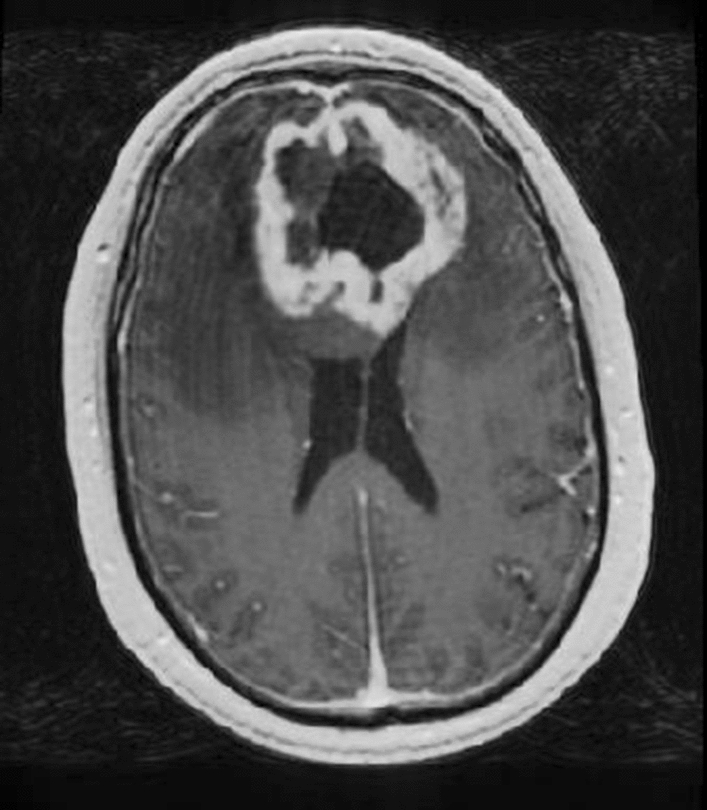

In the healthy brain, the blood–brain barrier (BBB) usually restricts exogenous contrast agents to the vascular bed. These agents are commonly based on low-molecular-weight gadolinium and locally shorten the T1 relaxation times allowing for better contrast between regions with and without the contrast agent. Disruption of the BBB, e.g., caused by glioblastoma, can lead to accumulation of these agents in the interstitial spaces surrounding the leaky vasculature [27]. As shown in Fig. 2, accumulation can be seen as an increase in signal intensity on T1-weighted MR imaging. Contrast enhancement on this conventional MR image is currently used as a surrogate measure of malignancy and can be indicative of high-grade gliomas [28, 29]. In various studies, progression-free survival and overall survival for both low-grade and high-grade glioma patients were observed to be worse when contrast enhancement was present [3034]. In current clinical practice, enhancing areas on gadolinium-based contrast-enhanced T1-weighted MR imaging are by default included in the GTV delineation of glioblastoma patients [3].

Fig. 2

Post-gadolinium-based contrast-enhanced T1-weighted axial image shows a ring enhancing lesion, in this case a glioblastoma. The peripheral enhancement is caused by accumulation of the contrast agent due to disruption of the BBB